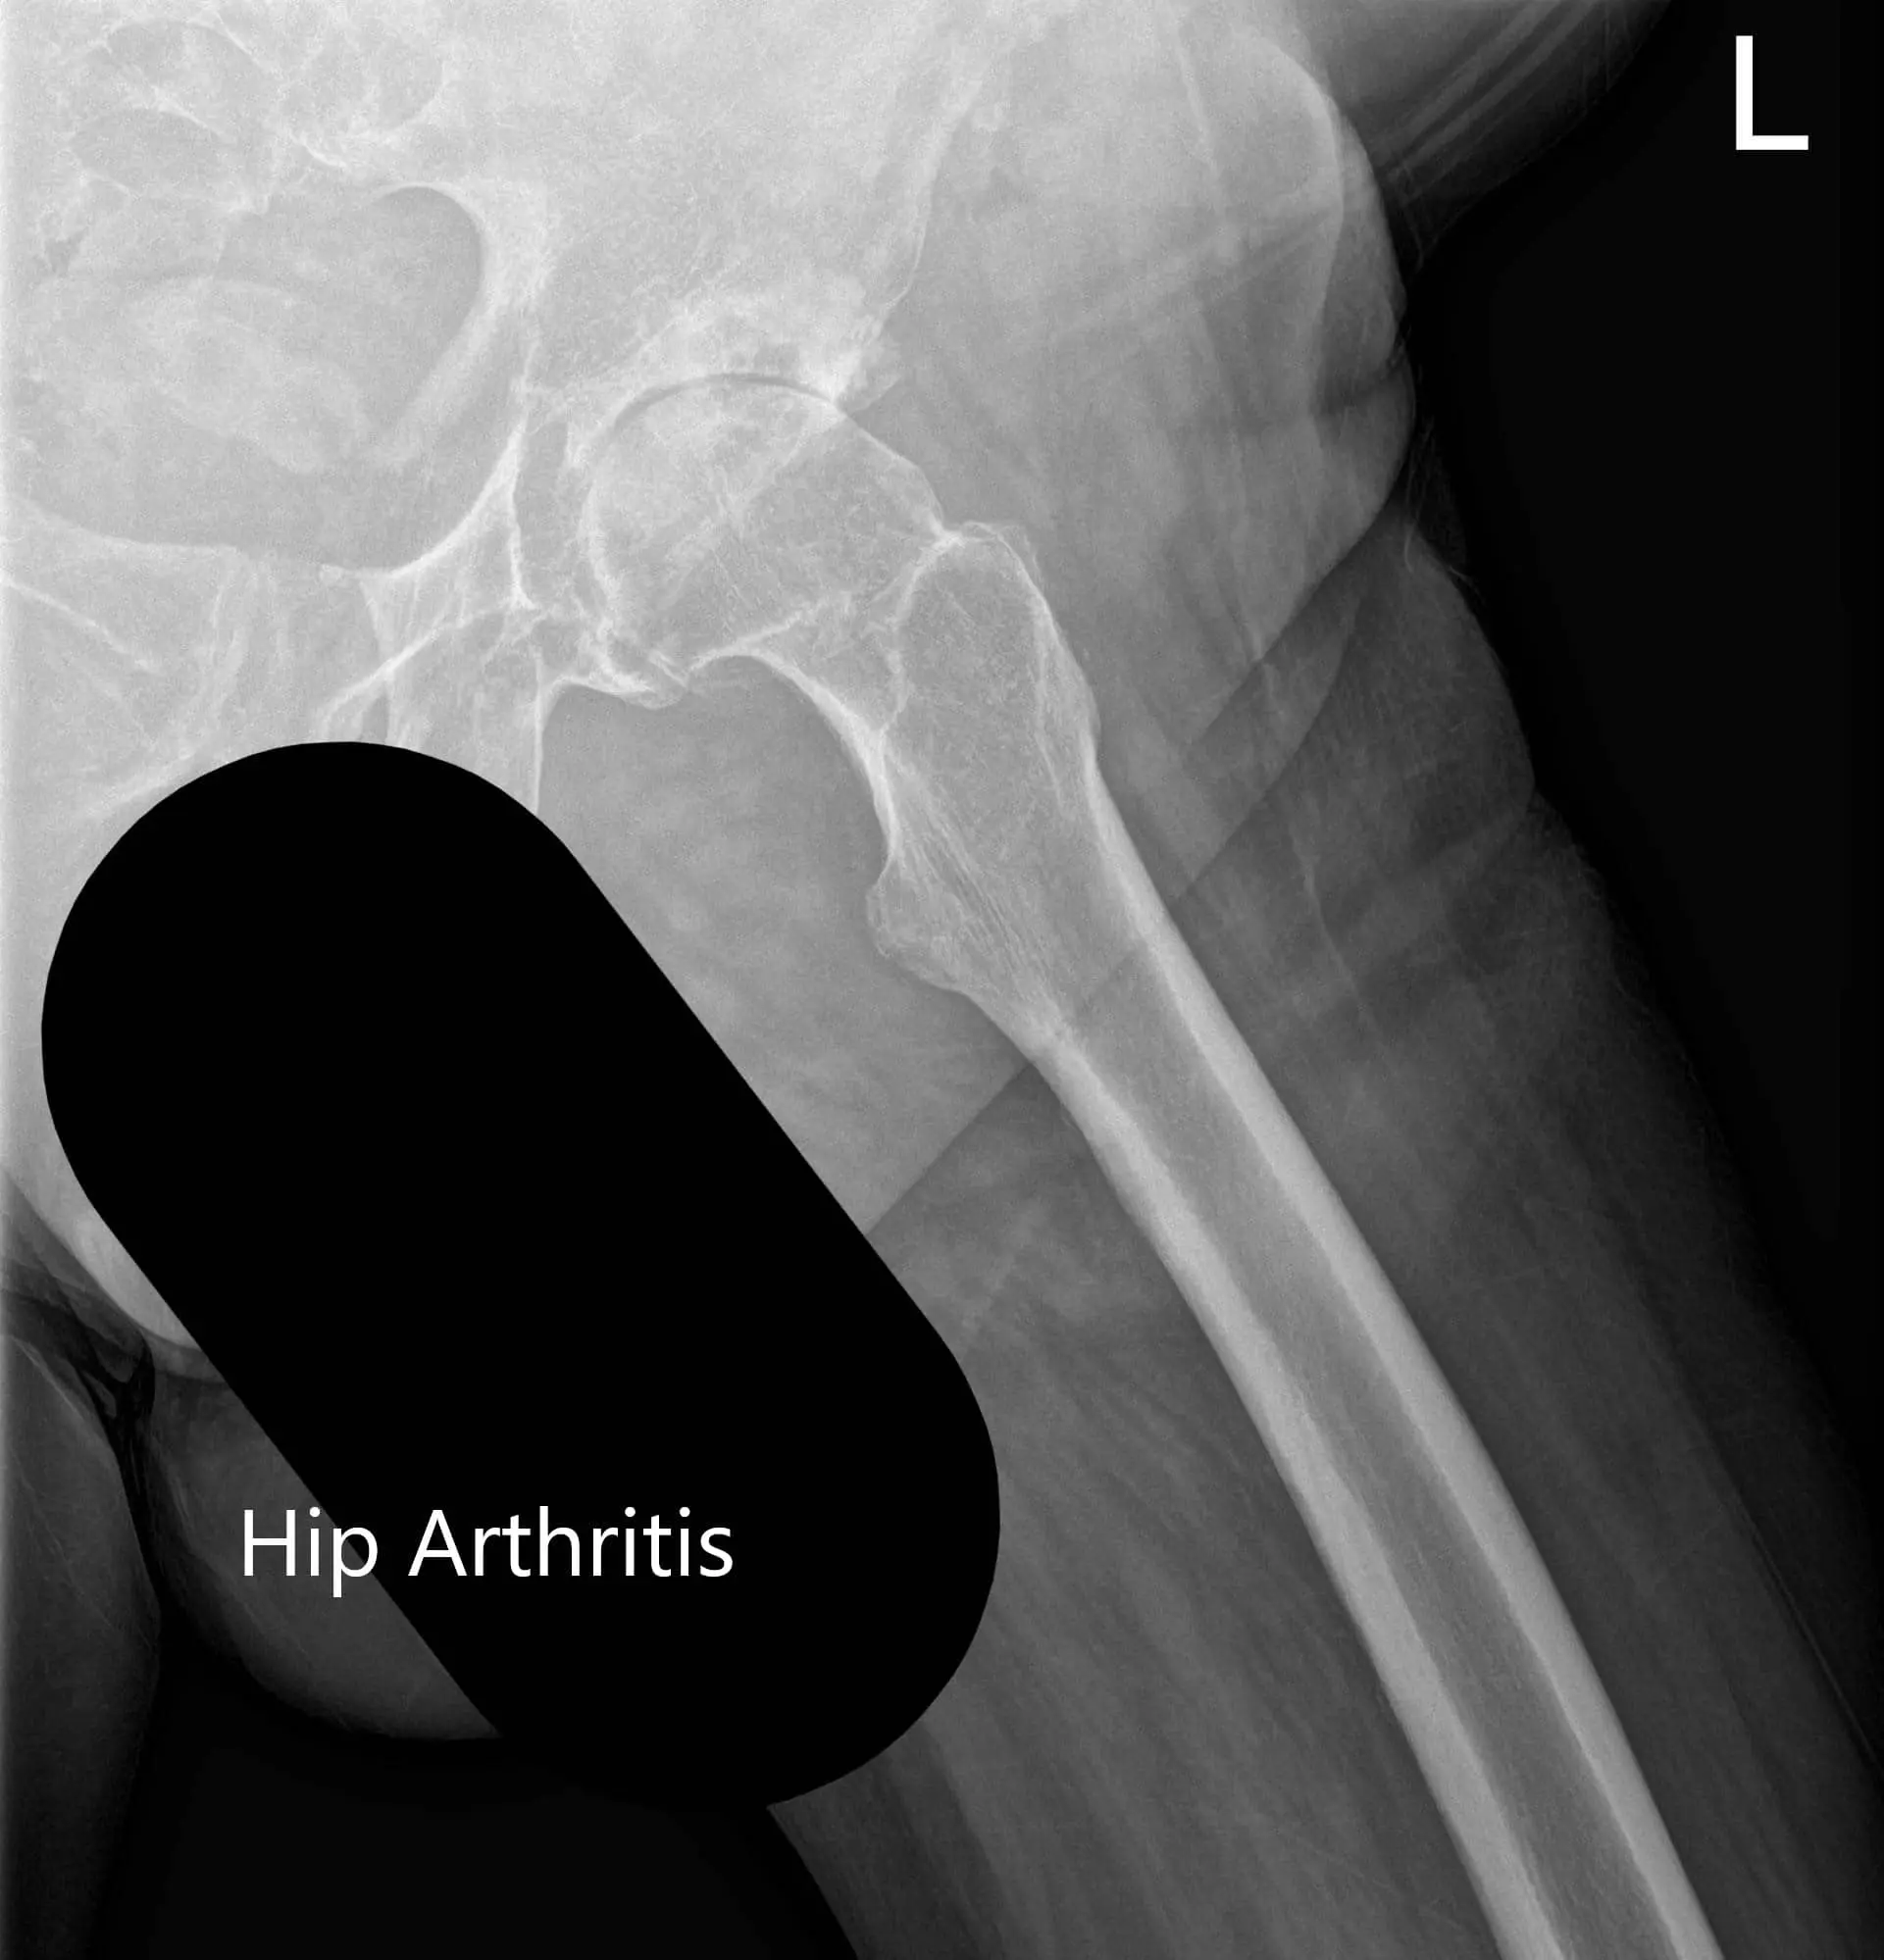

Preoperative X-ray showing the frog-legged lateral and AP view of the left hip 2

Preoperative X-ray showing the frog-legged lateral and AP view of the left hip

Preoperative X-ray showing the frog-legged lateral and AP view of the left hip - img 2

Preoperative X-ray showing the frog-legged lateral and AP view of the left hip.